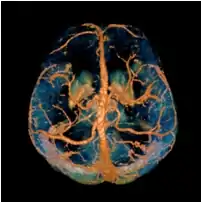

Quantitative susceptibility mapping (QSM) provides a novel contrast mechanism in magnetic resonance imaging (MRI) different from traditional susceptibility weighted imaging.[1][2][3][4][5] The voxel intensity in QSM is linearly proportional to the underlying tissue apparent magnetic susceptibility, which is useful for chemical identification and quantification of specific biomarkers including iron, calcium, gadolinium, and super paramagnetic iron oxide (SPIO) nano-particles. QSM utilizes phase images, solves the magnetic field to susceptibility source inverse problem, and generates a three-dimensional susceptibility distribution. Due to its quantitative nature and sensitivity to certain kinds of material, potential QSM applications include standardized quantitative stratification of cerebral microbleeds and neurodegenerative disease, accurate gadolinium quantification in contrast enhanced MRI, and direct monitoring of targeted theranostic drug biodistribution in nanomedicine.

COSMOS assumes a model-free susceptibility distribution and keeps full fidelity to the measured data. This method has been validated extensively in in vitro, ex vivo and phantom experiments. Quantitative susceptibility maps obtained from in vivo human brain imaging also showed high degree of agreement with previous knowledge about brain anatomy. Three orientations are generally required for COSMOS, limiting the practicality for clinical applications. However, it may serve as a reference standard when available for calibrating other techniques.